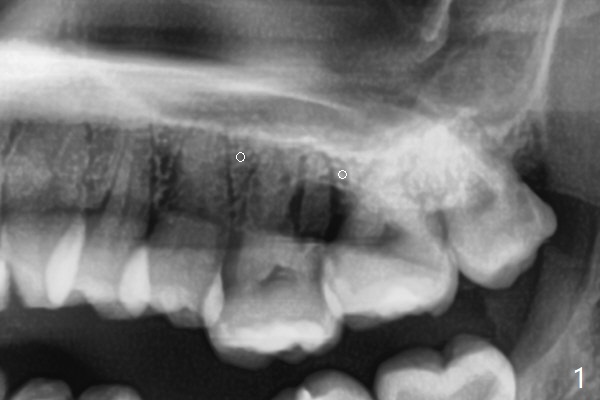

矫正器放置后一个月,正好有充裕时间,匆忙研究全景片(最好CT),好像左上6近中间隙大,近中颊侧,远中腭侧似乎是种植位点(图一:白圆圈),植入越高越宽,不容易伤及邻牙牙根。但是微型植体种植原则是必须种植在角化龈,减少炎症(以前不明白为什么)。当植体在移动牙龈植入时(图二:白箭头),牙龈浮起来,估计非角化牙龈也不能与植体产生紧密结合。取出后,完全可以在6近中颊侧角化龈植入,但是仔细检查发现远中颊侧角化龈更宽,所以在那里扎根(图二:黑箭头),因此腭侧就得选择近中(图三)。微型植体可以即刻使用,power chains常滑脱,压迫牙龈,在这个病例很可能进入远中牙间隙,所以需要在远中边缘嵴加树脂(图四,五:* (1.6x8mm))。第二天远中颊侧植体松动,取出后,插入2x10毫米一段式植体,仍然松动(图六)。CT显示植体下缘穿破牙槽骨(图七,骨质吸收严重与图八近中牙槽骨高度对比)。如果在近中颊侧重新植入微型植体,必须使用6毫米长植体(图九),所以最好在远中颊侧重新植入(图十:红色),缺损区(黑色)植骨。在使用14 niti时,左下7松动,病人同意拔除8,以后后推7,然后6种植(图十一:(左上8已拔除(x))),同时左上6远中植骨,左下8远中牙槽窝放置浸泡PRF液体胶原塞(图十二:1),近中牙槽窝粘性骨粉(2),最后牙槽窝上部PRF膜(3),PGA缝线。可能需要Cytoplast。